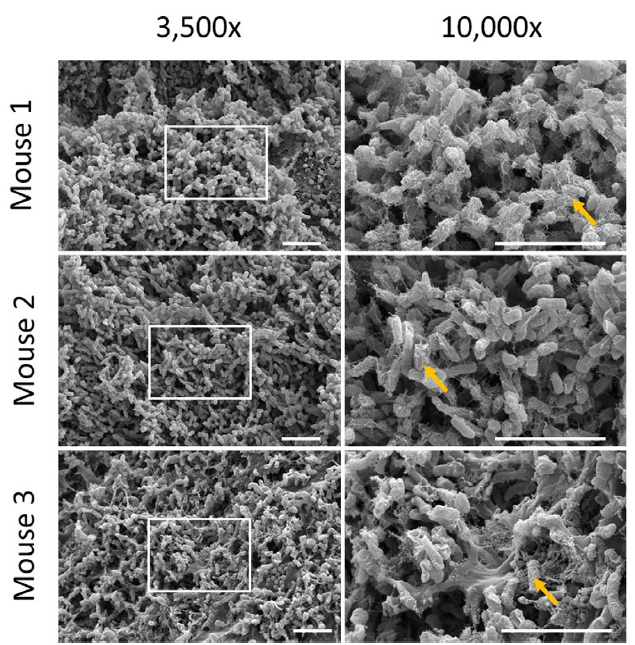

Detection of bacterial fluorescence from in vivo wound biofilms using a point-of-care fluorescence imaging device

Lopez, AJ et al. Int Wound J 2021